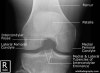

3. Lateral Knee View

Demonstrates: femorotibial articulation, patellofemoral articulation, Femoral condyles should be superimposed.

Helpful for: Knee Arthritis, Tibial Plateau Fracture, Distal Femur Fracture, Patellar Fracture, Patellofemoral Arthritis

Position: lateral with affected side down and flexed 30° at the knee. The contralateral leg is shifted posteriorly out of the way.

Beam directed at knee joint with 5° cephalad angulation.